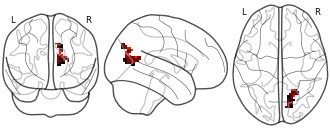

"name": "Multi_VBMgreater_fMRIenhanced",

"description": "Multi-modal analysis in BPD. Brain regions exhibiting greater gray matter and enhanced activation during emotion processing in BPD compared to healthy controls. Note: Results were thresholded at p<.0025. Note2: Results were updated (see Erratum for this publication).",